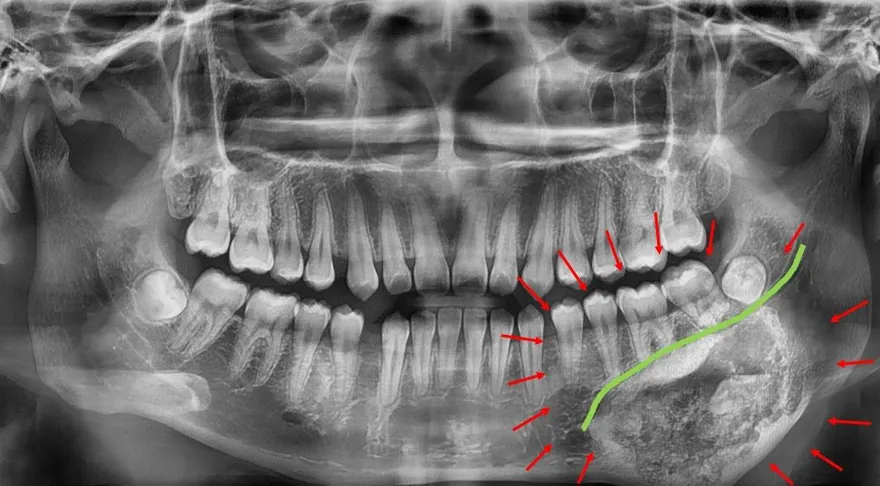

牙骨質骨化纖維瘤

顎骨腫瘤

3D列印重建手術

彰化秀傳紀念醫院

口腔顎面外科

腓骨皮瓣重建

ALL-ON-X植牙

顎骨重建手術